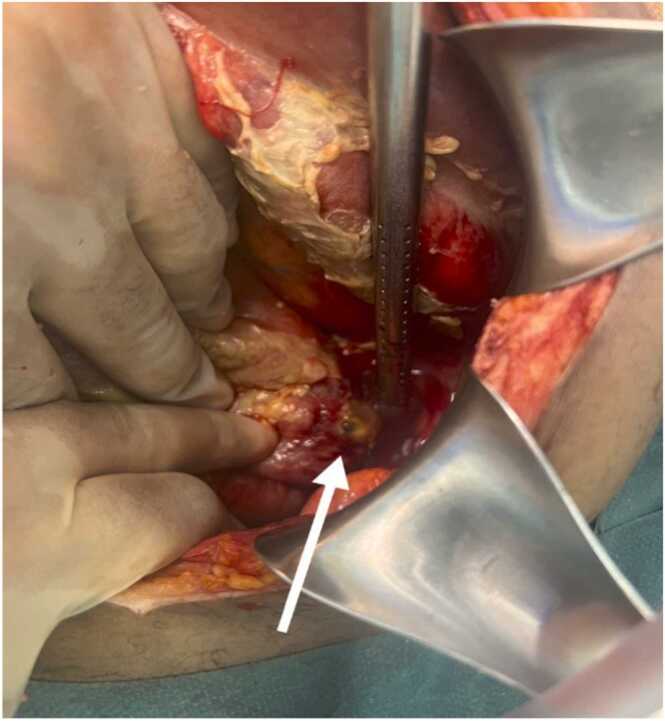

Abstract Image